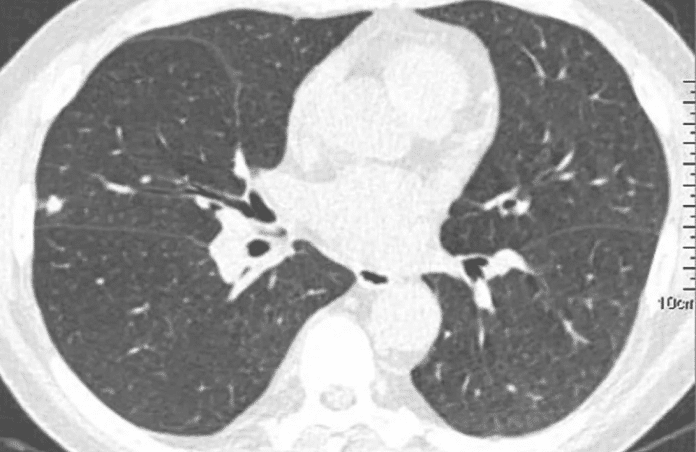

CT scan longen. Foto: archief.